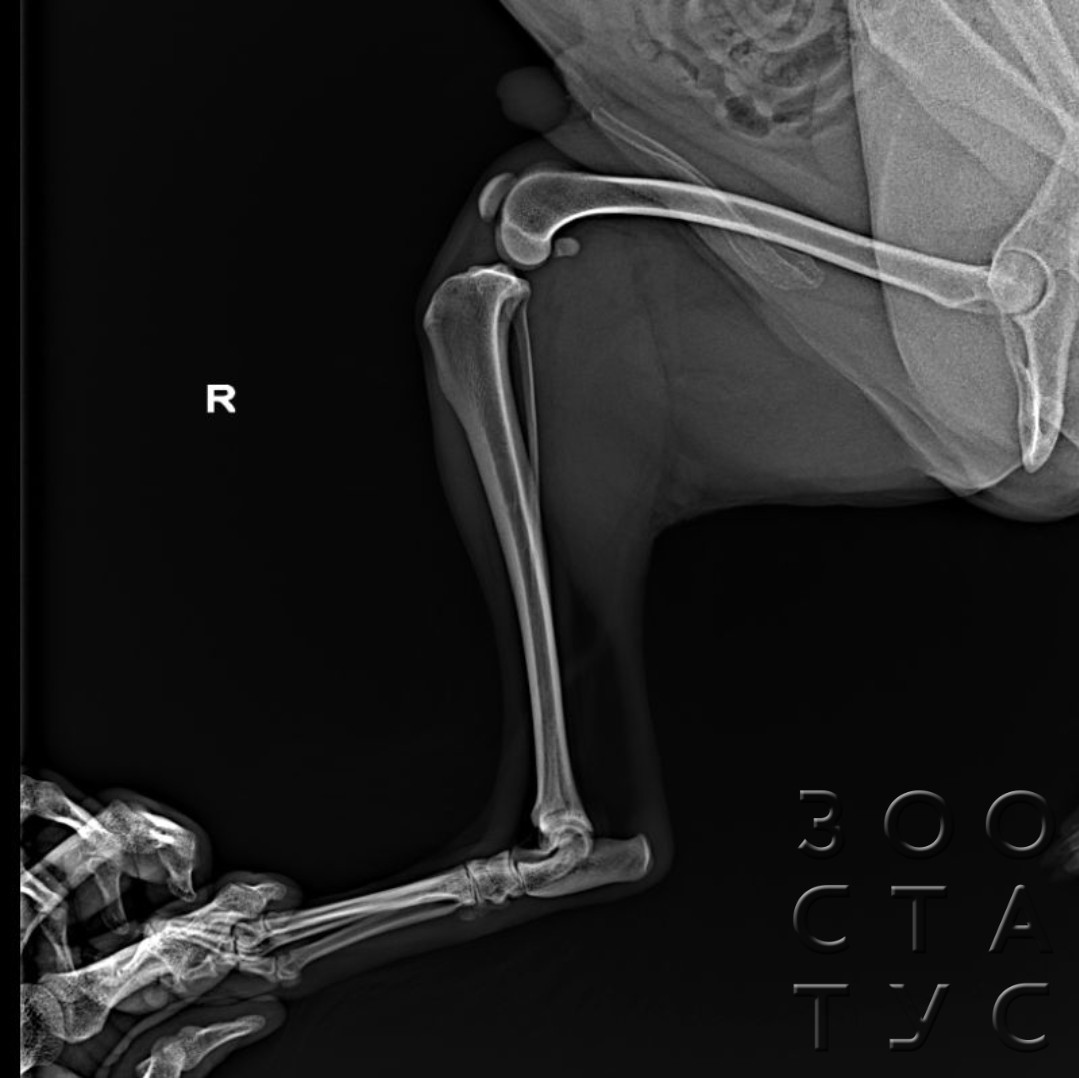

Рентген Задней Лапы Кошки: Нормы и Диагностика